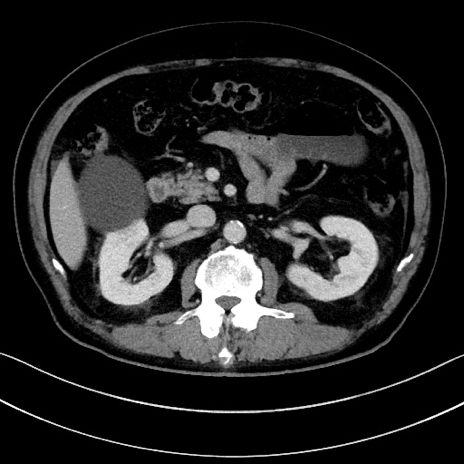

症例15(横断像)

【症例】70歳代男性

【主訴】腹痛

【現病歴】今朝から腹痛あり。全体的に痛い。特に左上の方。排ガスが今日はない。冷や汗が出る。

【既往歴】直腸癌術後

【身体所見】左側腹部〜上腹部に圧痛あり。腹膜刺激症状明らかなではない。軽度反跳痛。左下腹部に術後瘢痕あり。

【データ】WBC 7700、CRP 0.02